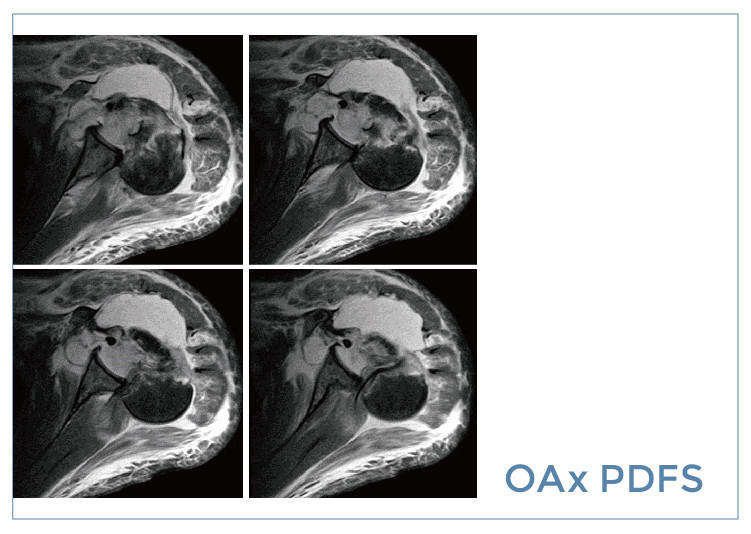

【朗润影像档案】磁共振影像病例分享(编号20190830)